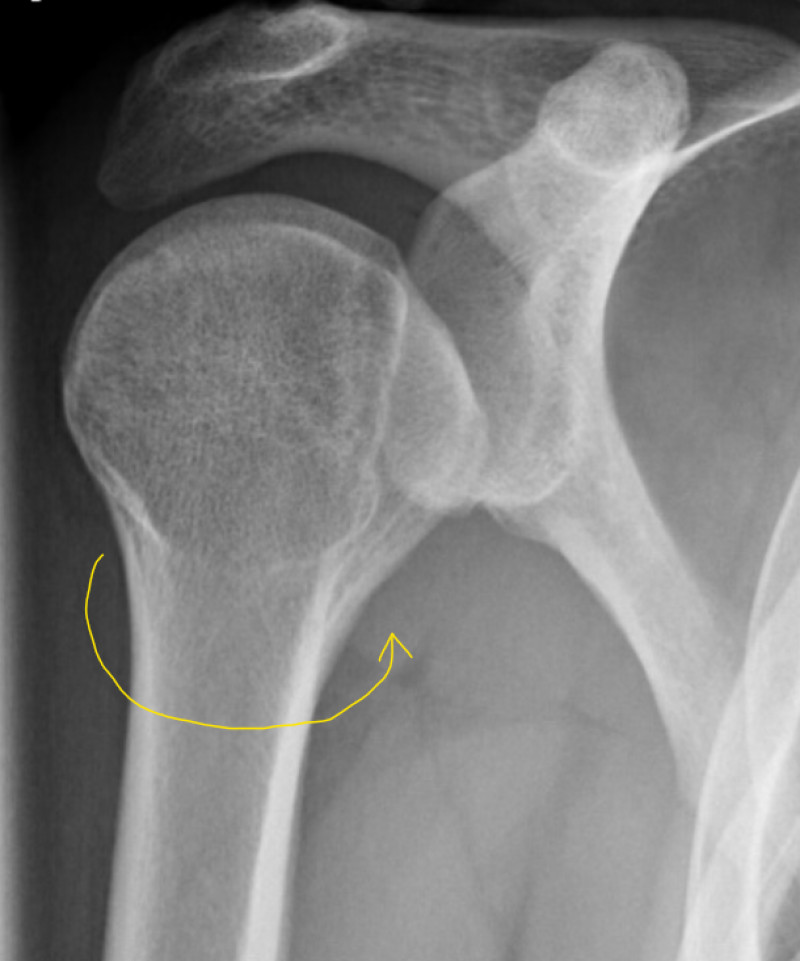

Fig 46. XRay Posterior Dislocation Cambridge Shoulder X Ray Posterior Shoulder Dislocation The humeral head is subcoracoid in. Posterior dislocation may be missed initially on frontal radiographs in 50% of cases, as the humeral head appears to be almost normally aligned with the glenoid 1,2. In adults, convulsive disorders are the most common cause. The axillary lateral view is the most accurate radiographic image to diagnose a posterior shoulder dislocation. This view. X Ray Posterior Shoulder Dislocation.

Posterior shoulder dislocation and reverse HillSachs Radiology Case X Ray Posterior Shoulder Dislocation Posterior dislocation may be missed initially on frontal radiographs in 50% of cases, as the humeral head appears to be almost normally aligned with the glenoid 1,2. In adults, convulsive disorders are the most common cause. Anteroposterior radiograph shows luxatio erecta, or inferior dislocation of the shoulder. The humeral head is subcoracoid in. The axillary lateral view is the most. X Ray Posterior Shoulder Dislocation.

Posterior shoulder dislocation with lesser tuberosity fracture Image X Ray Posterior Shoulder Dislocation Electrocution is a classic but uncommon cause of posterior. The humeral head is subcoracoid in. Posterior dislocation may be missed initially on frontal radiographs in 50% of cases, as the humeral head appears to be almost normally aligned with the glenoid 1,2. The axillary lateral view is the most accurate radiographic image to diagnose a posterior shoulder dislocation. In adults,. X Ray Posterior Shoulder Dislocation.